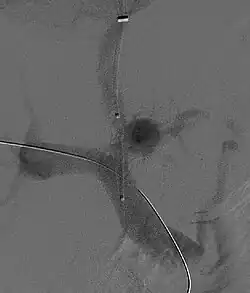

Derivação portossistémica intra hepática transjugular

O principal tratamento para hidrotórax hepático refratário é a inserção de uma derivação portossistémica intra hepática transjugular (sigla em inglês: TIPS). A TIPS descomprime o sistema portal, reduzindo a pressão venosa portal e o líquido no abdômen; estima-se que funcione em 70–80% dos casos. No entanto, não melhora o prognóstico em pacientes com doença hepática em estágio terminal.[8] Em pacientes com disfunção hepática grave, a TIPS pode causar insuficiência hepática, pois desvia o sangue do fígado.